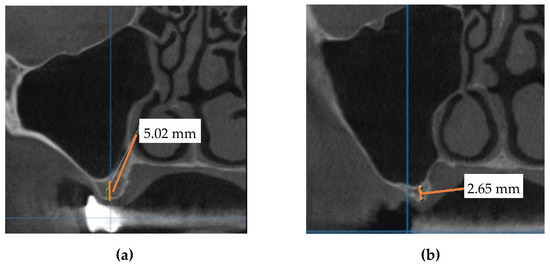

Following the described procedure, a comparison was made between the mezio-distal positions of the implant on the maxillary arch on the CBCT of the model and the patient’s postoperative CBCT, as shown in the panoramic views in Figure 7. Also, the distances from the top of the maxillary ridge to the lowest cut on the maxillary sinus buccal wall were measured on the cross-section in Figure 8.

Figure 7. Measurement of the mezio-distal position of the implant (i.e., distance from the anterior tooth to the middle of the implant (D1)) on (a) the training CBCT model (D1-3D) and on (b) the postoperative CBCT (D1-P)—panoramic view.

Figure 8. Measurement of the distance between the top of the ridge and the lowest access cut at the buccal wall of the maxillary sinus (for patient number 6 in Table 1) on (a) the training CBCT model (D2-3D) and on (b) the postoperative CBCT (D2-P) cross-section.